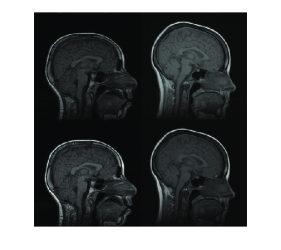

Another method to evaluate proposed registration method is visual examination of checkerboard images. Figure 10 shows an elastic registration example together with checkerboard image illustrating how well the image pair is registered. Checkerboard image includes white and black squares corresponding to intensity values taken from the registered source and the target image respectively. Our overall observation from experimental results is that multiresolution elastic registration on standard intensity scale can capture both local and global deformations with high accuracy.